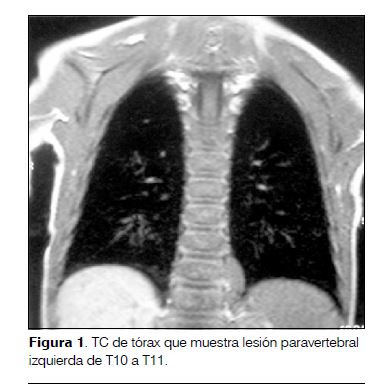

Comienza con irritabilidad, decaimiento y trastornos del sueño, agregando a las 48 horas ataxia con marcha inestable, aumento de la base de sustentación, alteración en la coordinación de miembros superiores y temblor cefálico. Ingresa en el Hospital de Salto presentando progresión de su sintomatología con pérdida de la bipedestación y sedestación independiente, alternancia de irritabilidad-somnolencia y vómitos reiterados. Se le realiza tomografía computada (TC) de cráneo (que fue normal) y punción lumbar con estudio del líquido céfalo-raquídeo. El estudio citoquímico fue normal, el virológico para virus de la familia herpes y enterovirus fue negativo. Se traslada al Centro Hospitalario Pereira Rossell donde se comprueba opsoclonus y polimioclonías (puntaje de la escala de SOM: 13/15). Con el planteo de SOM se inicia tratamiento con metilprednisolona e IgIV. Se realiza TC tóraco-abdómino-pélvica y resonancia magnética (RM) que muestran una lesión paravertebral izquierda de T10 a T11 que realza intensamente con el contraste, sin compromiso vertebral ni del canal raquídeo, compatible con el diagnóstico de neuroblastoma (figuras 1 y 2). El mielograma y el centellograma óseo con tecnecio 99 fueron normales.

Realizado el diagnóstico de SOM y, dado que en 45% de los casos se asocia a neuroblastoma, se debe proceder a la búsqueda del mismo(5). El protocolo de screening incluye: RM o TC de alta resolución de tórax, abdomen y pelvis, en los casos en que presentan un síndrome de Horner hay que realizar también imagen cervical; dosificación urinaria de catecolaminas (ácido vanilmandélico y homovanilmandélico) y centellograma con I123-metilodobenzilguanidina (MIBG)(1,6,7,9). En nuestro caso la TC y la RM evidenciaron la presencia de un neuroblastoma torácico, localización descripta como más frecuente (55%), sin evidencias de diseminación en el centellograma. Como el SOM puede preceder la aparición del neuroblastoma, de no encontrarse al momento del diagnóstico se recomienda continuar su búsqueda realizando RM cada 6 meses por 2 años(4). Realizado el diagnóstico del neuroblastoma se impone su tratamiento oncológico específico: cirugía y/o quimioterapia. Los síntomas neurológicos no necesariamente mejoran con la resección del tumor observándose solo en 1/3 de los casos y por lo tanto es necesario un tratamiento sintomático. Los fármacos más frecuentemente utilizadas son inmunosupresores e inmunomoduladores(3,10).